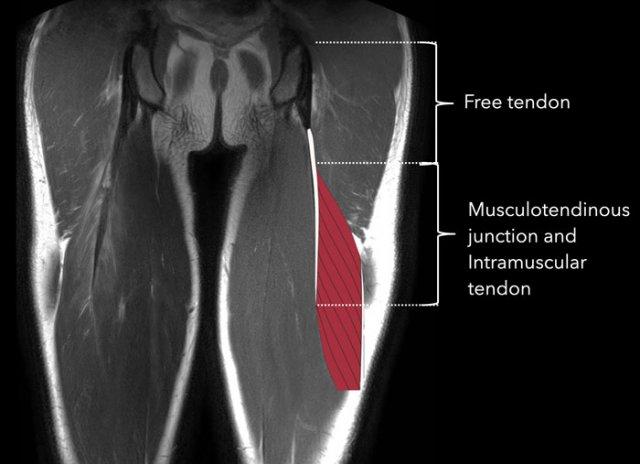

Hình ảnh giải phẫu được minh họa trên ảnh MRI mặt phẳng coronal.

Điểm bám của cơ bán gân (2) vào nguyên ủy gân kheo có một phần là mô cơ.

Gân tự do bám vào ụ ngồi và không có sợi cơ nào bám vào nó.

Ranh giới giữa gân và các sợi cơ được gọi là chỗ nối cơ-gân (musculotendinous junction).

Phần gân có các sợi cơ bám vào được gọi là gân trong cơ (intramuscular tendon).

Bản thân cơ được bao bọc bởi mạc cơ (fascia).